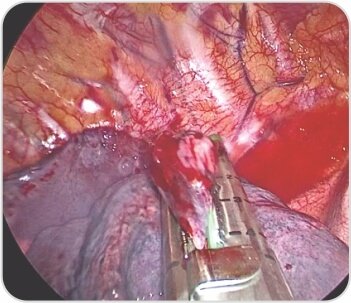

Right upper lobe apical segment bullae

Bullectomy with endostaplers